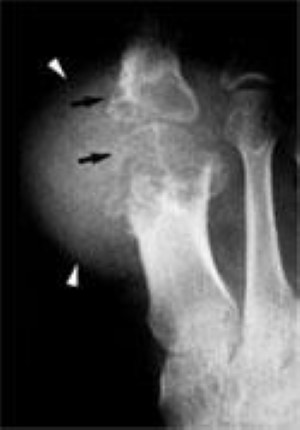

x-ray of advanced gout in big toe

This X-ray of a big toe shows advanced gout. The black arrows point to places where bone has worn away. The white arrows point to a tophi mass.

Reproduced from Johnson TR, Steinback LS [eds]: Essentials of Musculoskeletal Imaging. Rosemont, IL, American Academy of Orthopaedic Surgeons, 2004, p 627.